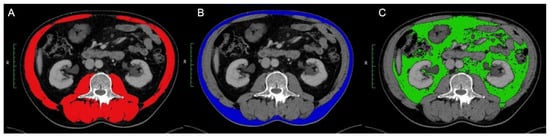

- Mourtzakis, M.; Prado, C.M.M.; Lieffers, J.R.; Reiman, T.; McCargar, L.J.; Baracos, V.E. A practical and precise approach to quantification of body composition in cancer patients using computed tomography images acquired during routine care. Appl. Physiol. Nutr. Metab. 2008, 33, 997–1006. [Google Scholar] [CrossRef]

- Zopfs, D.; Theurich, S.; Große Hokamp, N.; Knuever, J.; Gerecht, L.; Borggrefe, J.; Schlaak, M.; Pinto dos Santos, D. Single-slice CT measurements allow for accurate assessment of sarcopenia and body composition. Eur. Radiol. 2020, 30, 1701–1708. [Google Scholar] [CrossRef]